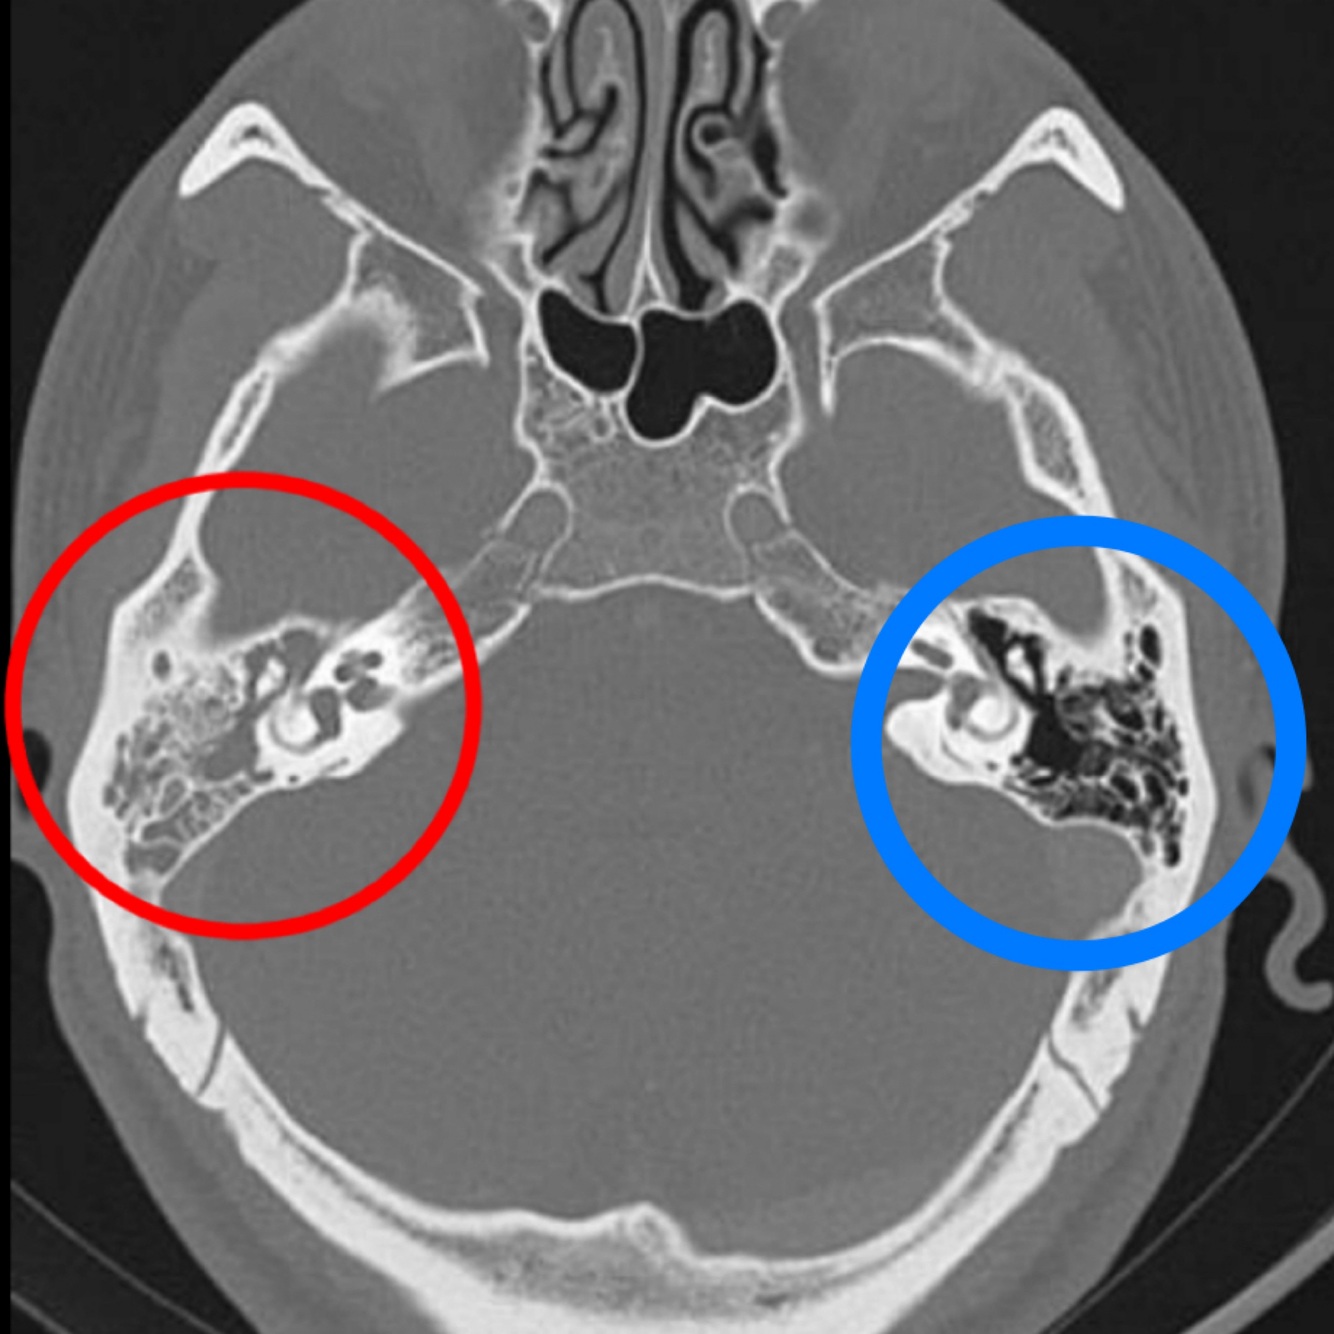

Hallazgos de TC:

• Opacificación de celdillas mastoideas

• Crónico: Esclerodiploico = engrosamiento óseo

Hallazgos en imagen:

RM o TC

• Otitis y mastoiditis

• Masa que destruye hueso

A (afectado): se pierden huesecillos